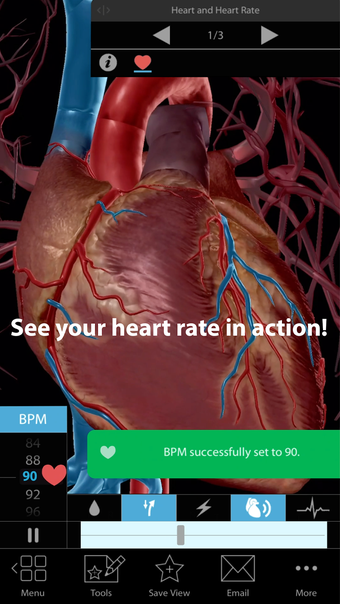

One of the most remarkable features of this application is that it enables users to compare 3D models of normal anatomy with models of common diseases and conditions. Furthermore, users can set the heart rate and visualize conduction in a dissectable, beating 3D heart while following along on an ECG. The application also presents animations that demonstrate the physiological processes of gas exchange, pulmonary ventilation, fluid balance, peristalsis, and more. Interactive lessons walk users through the progression of atherosclerosis, kidney stones, lung cancer, and other common conditions, and quizzes test users' knowledge of various physiological processes and pathologies.